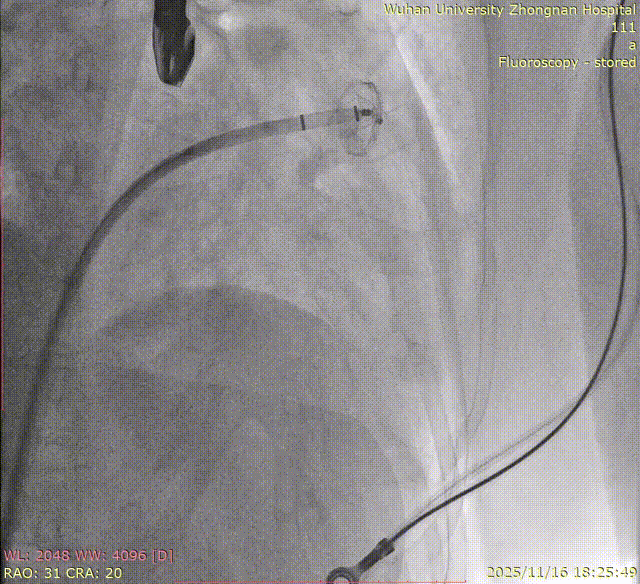

Left Atrial Appendage Closure (LAAC):The delivery system was successfully advanced into the left atrium. Precise measurements of the LAA orifice and depth were taken under multi-angle TEE and DSA guidance. Given the LAA's large orifice (nearly 34mm), conical cauliflower shape, and shallow usable depth, a LACBES2434 occluder was selected. Using the "extreme coin technique," the closure was successfully achieved.

DSA

5.Right coronary angiography confirming no impact on the RCA after clipping.

8.Right coronary angiography confirming no impact on the RCA before releasing the second implant.